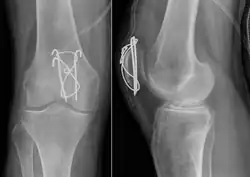

-

Transverse fracture of patella -

Comminuted fracture of patella -

Most patella fractures are transverse or comminuted, hence the quadriceps mechanism is disrupted and they are treated by a combination of wires in a tension band construct. This unites the fractured bones, reconstructing the straightening mechanism of the leg.[5][6]